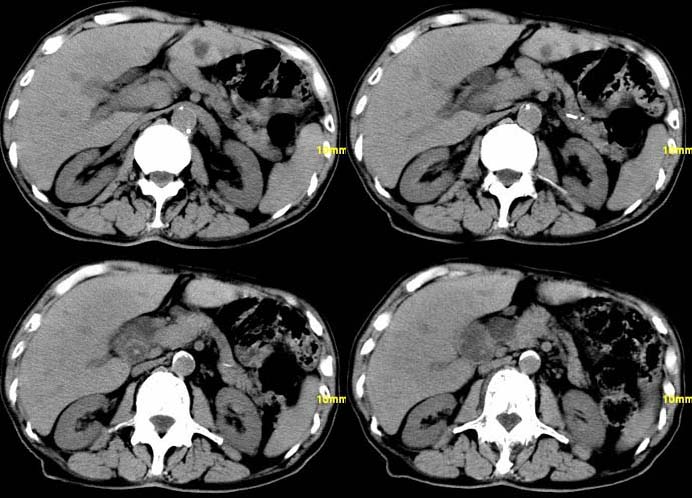

以下是引用余辉在2007-12-6 22:23:00的发言:[br]胆囊内多枚结石影,胆管全程扩张,右肝内病灶强化符合脓肿表现现(左肝病灶图像未传完),考虑急性梗阻性化脓性胆囊胆管炎合并肝多发脓肿(建议补传左肝病灶图像)